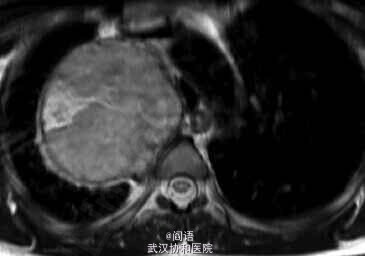

MRI扫描提示神经鞘瘤。

胸外科进行切除,组织学证实为神经鞘瘤。

患者表现为神经鞘瘤所引发的“丑角综合征(Harlequin syndrome)”。其特点是面部不对称性的潮红和出汗,即患侧的自主神经功能紊乱。本例单侧面部潮红多汗是由于肿瘤压迫颈部交感神经链所致。切除肿瘤后,症状显著改善。